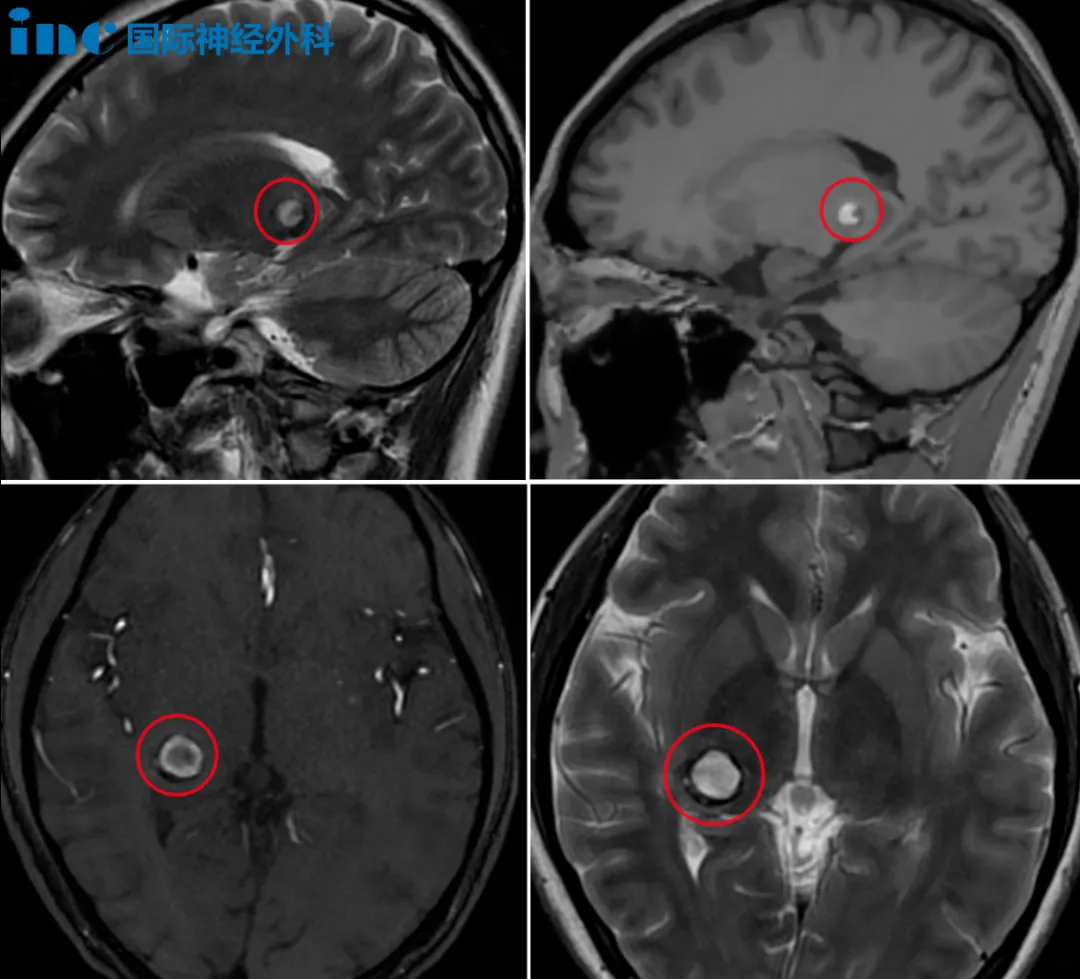

前天因为视野狭窄变模糊和持续性头痛,小雨和家人紧急就医,诊断结果却令一家人陷入绝望——丘脑海绵状血管瘤伴少量出血。这个陌生的病症,成为了这个家庭必须直面的生死考验。

CT检查的结果像一道惊雷:脑出血。进一步的头颅核磁检查更是给出了一个让全家陷入绝望的诊断——右侧丘脑海绵状血管瘤,伴少量出血。

2024年6月7日,复合手术室的无影灯亮起。巴教授凭借着对大脑解剖结构的精准掌握,以及多年积累的疑难手术经验,在显微镜下小心翼翼地分离着脑组织,一点点靠近位于丘脑的病灶。最终为小雨顺利全切病灶。